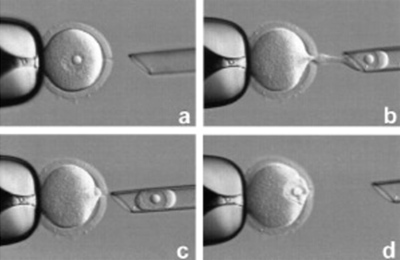

ĶŠģÕŖ®ÕŁĄÕī¢’╝łAssistedHatching’╝ē